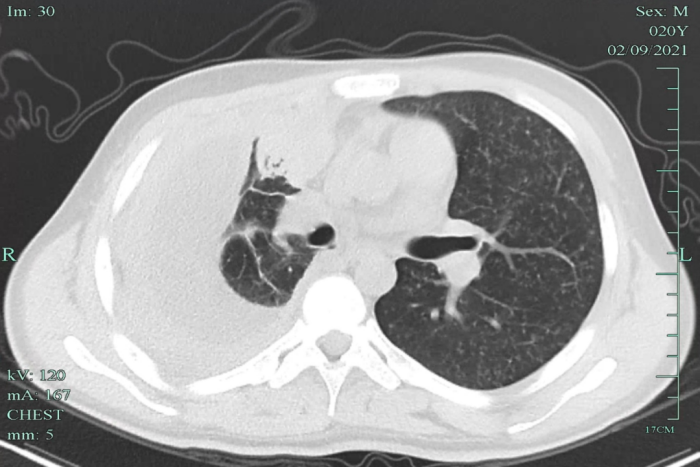

在當(dāng)?shù)蒯t(yī)院檢查,發(fā)現(xiàn)小明兩肺粟粒影,提示可能血行播散性肺結(jié)核,伴有胸腔積液,提示病程比較長了,炎癥反應(yīng)嚴(yán)重。小明立即來到我院感染科就診,隨后住院治療。

經(jīng)全面檢查,小明被診斷為“急性血行播散性肺結(jié)核、結(jié)核性滲出性膿胸”,該類型的肺結(jié)核非常容易引起其他部位的結(jié)核播散,雖然當(dāng)時小明沒有頭疼頭暈癥狀,但經(jīng)過頭顱磁共振檢查發(fā)現(xiàn),其顱內(nèi)有散發(fā)的結(jié)核病灶。